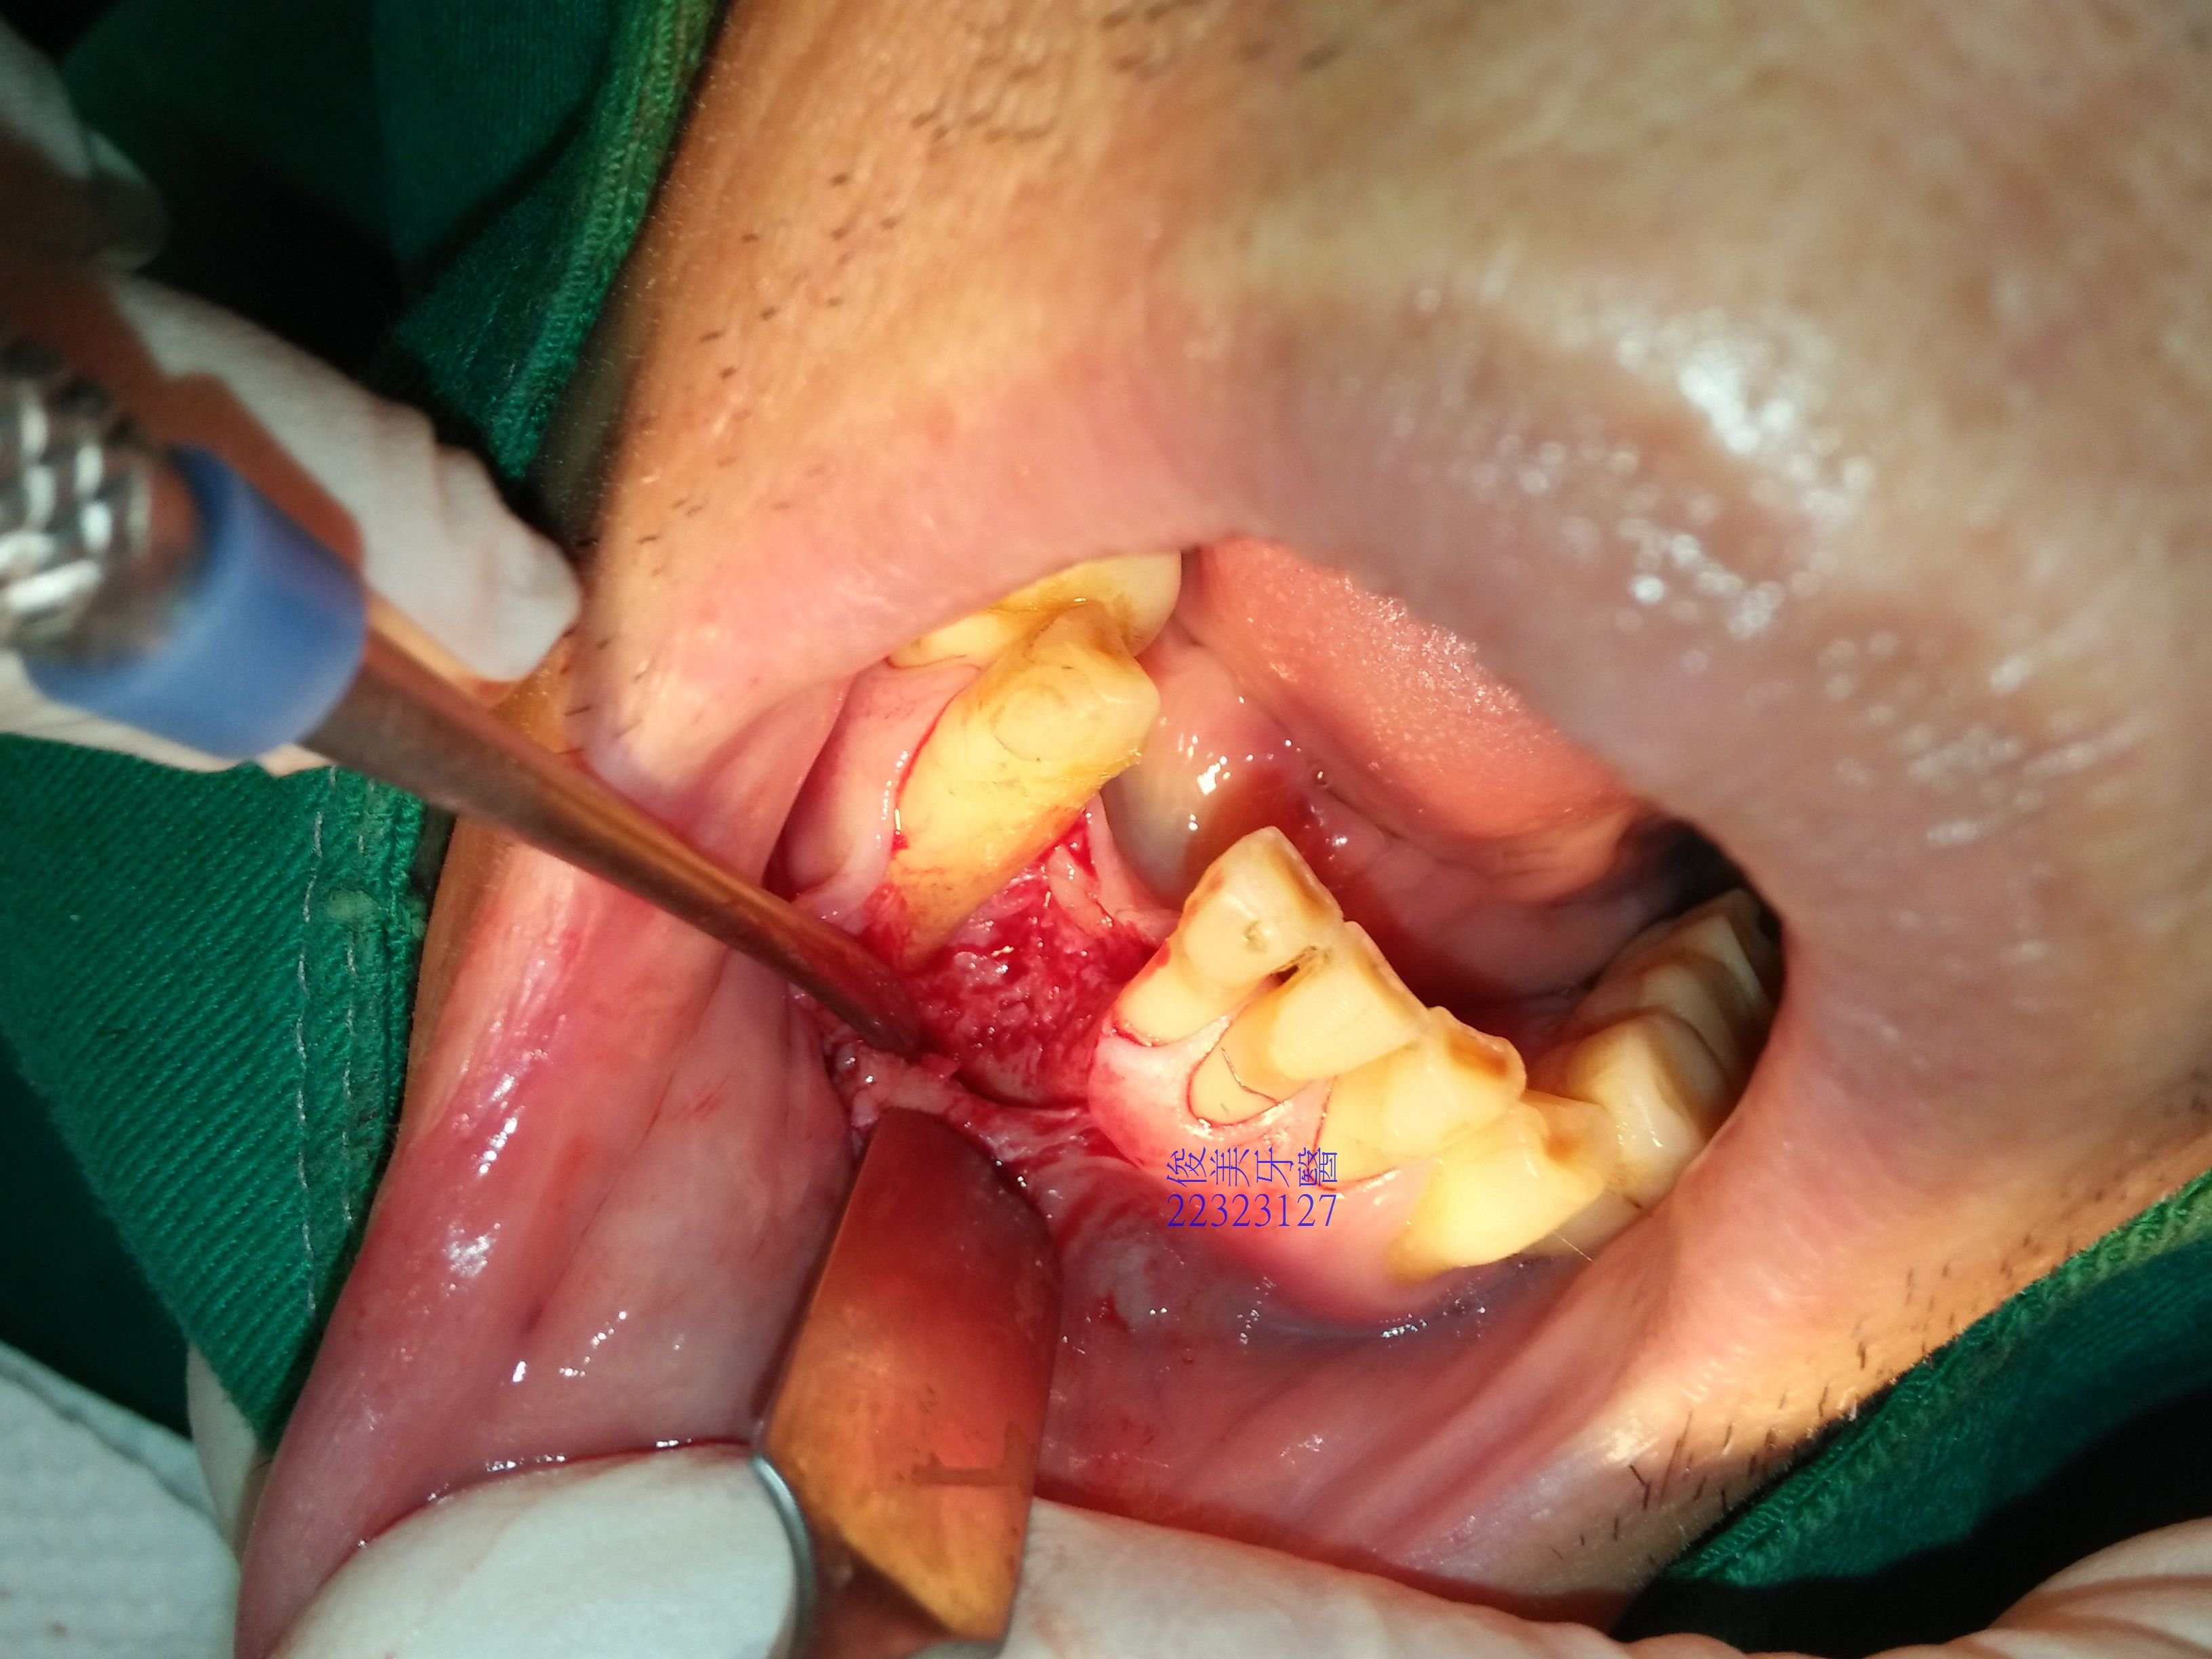

安排自體骨的移植手術。

患者骨脊很低,連帶隔壁犬齒的牙根也受到波及,移植骨塊時會一併保護了鄰牙的牙根。

從下顎智齒區取下骨塊,再移植至前牙區,利用特殊骨釘固定,讓自體骨塊癒合、生長。